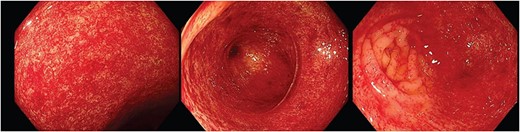

Endoscopic images depicting macroscopic findings of PHC including vascular ectasias and nonspecific inflammatory mucosal changes leading to friable mucosa which bled on contact.

Figure 2 depicts the macroscopic findings encountered that led to this exceptional diagnosis of PHC by an experienced endoscopist. The endoscopic mucosal changes are non-specific inflammation and subtle vascular changes, which are important features described in literature [1]. These were noted by the histopathologist microscopically but were unable to provide a diagnosis. This scenario often presents many endoscopists and histopathologists a significant challenge as the variations in endoscopic descriptions and the absence of uniform diagnostic criteria/classifications in literature can make a definitive diagnosis especially difficult. In these cases, clinicians often rely on patient history to identify a possible underlying cause for the endoscopic findings, such as alcohol misuse.